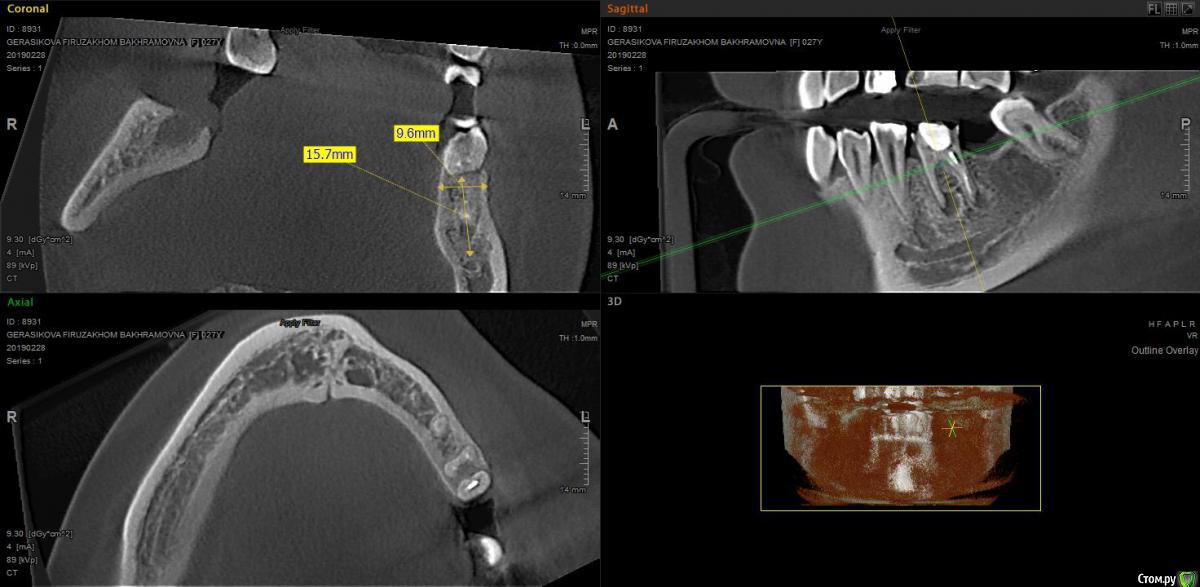

moises Опубликовано 13 марта, 2019 Автор Поделиться Опубликовано 13 марта, 2019 Чтобы не плодить темы,напишу здесь.Та же пациентка,противоположный сегмент.Планируется удаление 36 и имплантация 36,37.Стоит идти одномоментно?Зуб резорцин,бессимптомный Ссылка на комментарий